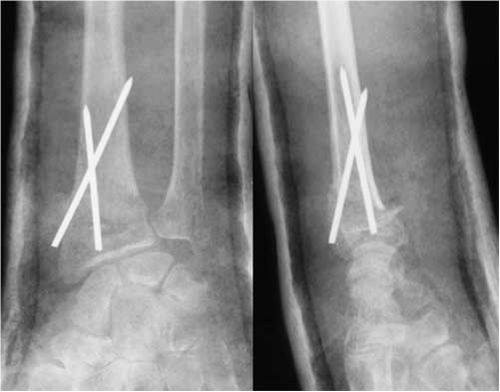

Aujourd'hui, cours sur les fractures de l'extrémité inférieure du radius. Retenez juste qu'elles touchent surtout les femmes ostéoporotiques et les jeunes hommes (AVP). Si ça ne bouge pas trop, on plâtre ; si ça ressemble à un puzzle, on réduit puis on ostéosynthèse avec quelques broches. Voilà, vous savez tout...